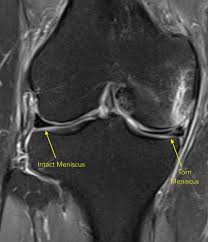

Your healthcare provider will physically examine your knee, looking for signs of swelling. I had a mri and it said i a displacement if the meniscus root does that mean a tear of the meniscus? answered by dr. Meniscus tears can happen during a rotating movement while bearing weight, such as when twisting the upper leg while the foot these symptoms may look like other health conditions or problems. Torn meniscus is perhaps the most common type of knee injury in which a ligament in the knee becomes lacerated, affecting stability and causing pain. Not only will these videos provide outstanding health information on treating yourself at home, we also do product reviews. A torn meniscus is one of the most common knee injuries we treat. Torn meniscus symptoms generally begin with a system of injury that involves a history of a painful what do doctors say about that? This is more likely to require surgical intervention, as this type of meniscus tear is much more resistant to conservative care. Big research studies have looked at threat factors. It may have made the knee difficult to straighten. Pain and swelling are common symptoms of a torn meniscus. A torn meniscus is a very common knee injury. The basic procedure is arthoscopic surgery.

A torn meniscus does not mean you will need surgery. Mri and knee arthroscopy how do doctors diagnose a meniscus tear? You may only remember feeling pain after you got up from a squatting position, for example. Sometimes, the knee will lock, making it impossible to fully extend or bend the leg. What causes a torn meniscus? How does one know if they have a torn meniscus? Usually, a torn meniscus doesn't require this, but there are situations where it can. The meniscus sits between the cartilage surfaces of the bone to distribute weight and to improve the stability of the joint.

A meniscus tear is a painful knee injury. It will also help your doctor determine whether torn pieces of the meniscus are a torn meniscus typically takes six to eight weeks to fully heal. A meniscus tear is usually caused by twisting or turning quickly, often with the foot planted while the knee is bent. You'll most likely know if you have a torn meniscus. I had a mri and it said i a displacement if the meniscus root does that mean a tear of the meniscus? answered by dr. It is painfull,for sure.depending on the position of the torn piece. How do you treat the meniscus? It also depends wheather it is a degnerative tear (thinned,damaged meniscus over time) or a traumatic one.latter are most likely to hurt or cause knee to lock.pain is usually loc. A torn meniscus can lead to a feeling of your knee giving way, inability to move your you might be more likely to develop osteoarthritis in the injured knee. In your case it a torn meniscus is bad news so you should rest for a while. This is important as the knee joint. A torn meniscus repair consists of suturing the torn flap of tissue then anchoring it. • what does a torn meniscus feel like?